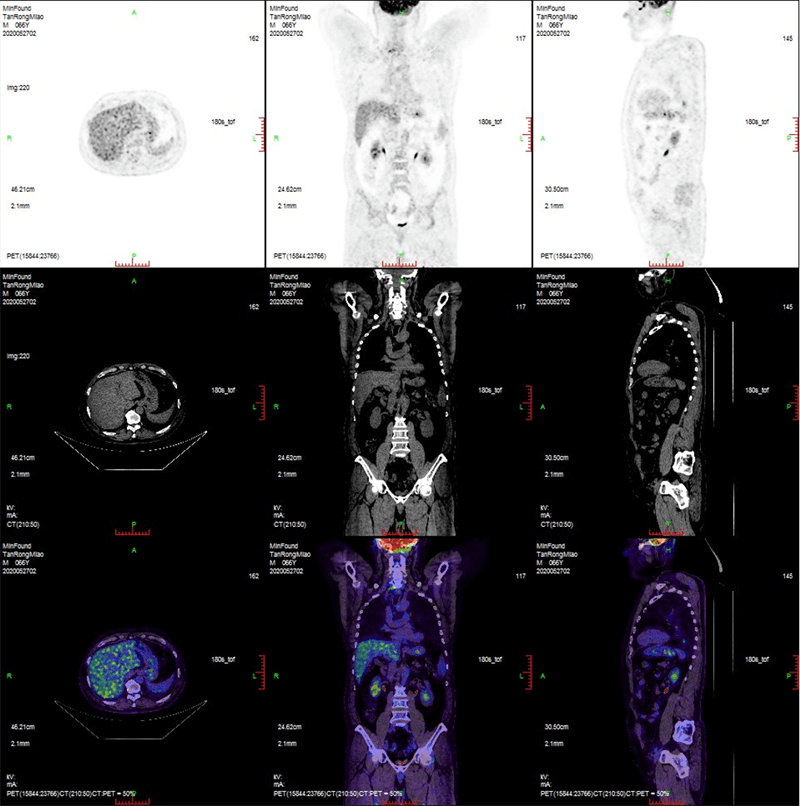

Clinical Gallery